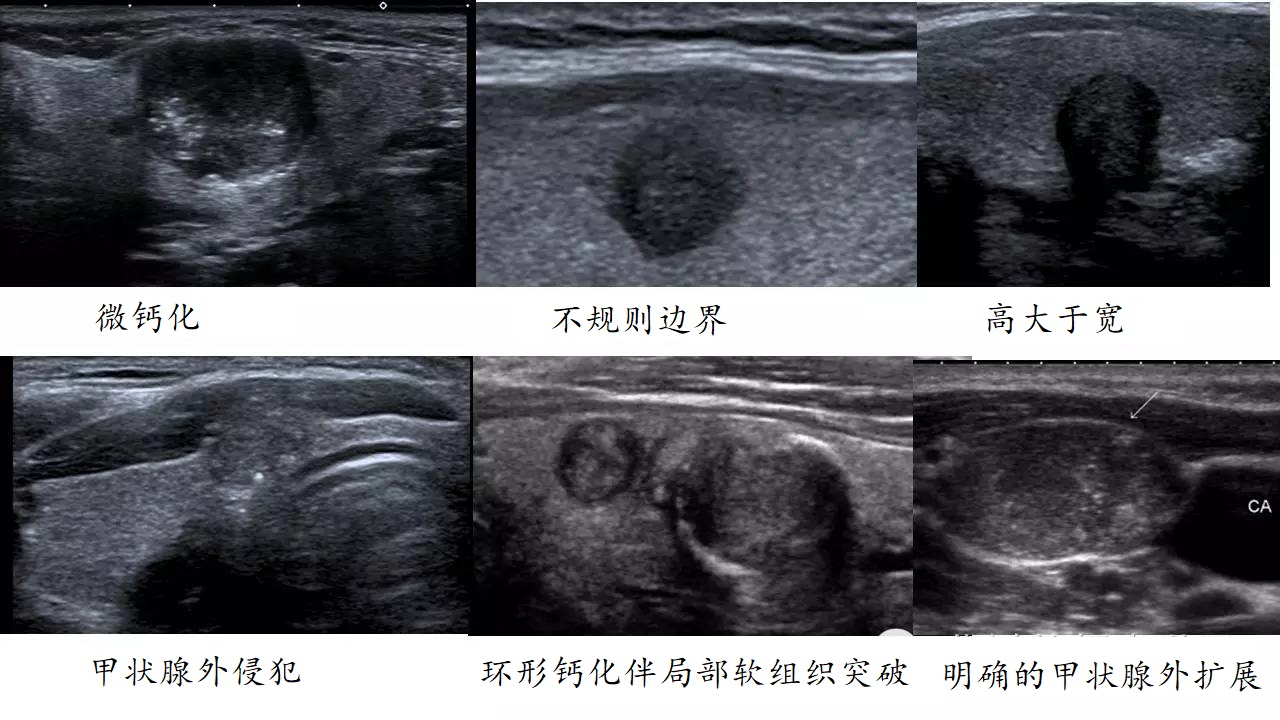

✅ 第1关:B超显神通

"彗星尾征"=天使结节(放心睡!)

"毛刺状边缘"+低回声+微钙化=危险信号灯!